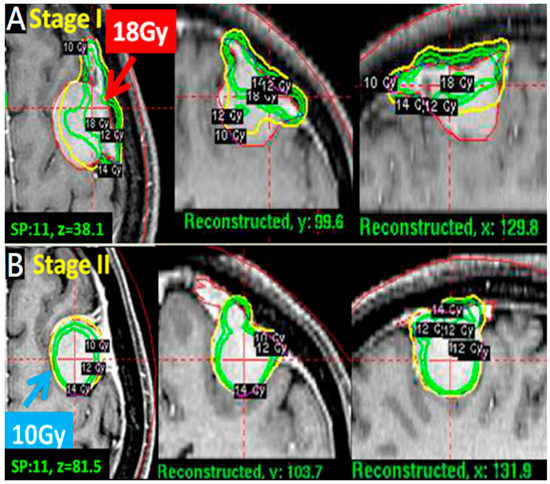

2.2. Treatment Approach and Exposure Variable